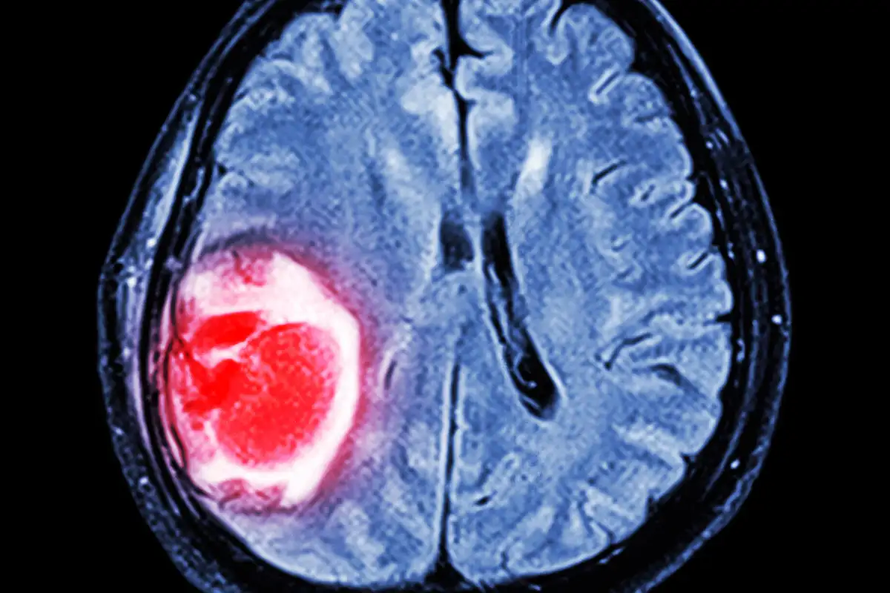

AI giúp phân loại khối u não chỉ trong vài giờ

(Ngày Nay) - Một nhóm nghiên cứu thuộc Đại học Quốc gia Australia (ANU) đã phát triển một công cụ trí tuệ nhân tạo (AI) có thể phân loại các khối u não nhanh và chính xác hơn.

Trong một nghiên cứu được công bố vào ngày 17/5, nhóm nghiên cứu đã chứng minh mô hình học sâu của họ – DEPLOY – có thể phân loại chính xác các khối u não thành 10 loại. Theo đó, công cụ AI đã phân tích hình ảnh hiển vi của mô não bệnh nhân để phân loại.

Nếu việc chẩn đoán và phân loại khối u não hiện nay dựa trên quá trình methyl hóa ADN mất khoảng vài tuần, thì công cụ AI có thể cho ra kết quả chỉ trong vài giờ. Đáng chú ý, DEPLOY còn cho kết quả chính xác cao chưa từng có, lên tới 95%. Khi được cung cấp 309 mẫu đặc biệt khó phân loại, DEPLOY có thể đưa ra chẩn đoán phù hợp hơn về mặt lâm sàng so với chẩn đoán mà các nhà nghiên cứu bệnh học đưa ra ban đầu.

Theo các nhà nghiên cứu, DEPLOY đã được đào tạo và xác nhận trên tập dữ liệu gồm khoảng 4.000 bệnh nhân từ Mỹ và một số nước châu Âu. Công nghệ này có thể được sử dụng trong tương lai để bổ sung vào chẩn đoán ban đầu của các nhà nghiên cứu bệnh học hoặc là cơ sở để xem xét lại nếu có sự không tương đồng. Hơn thế nữa, các nhà nghiên cứu còn kỳ vọng công nghệ AI này có thể giúp phân loại các ung thư khác.